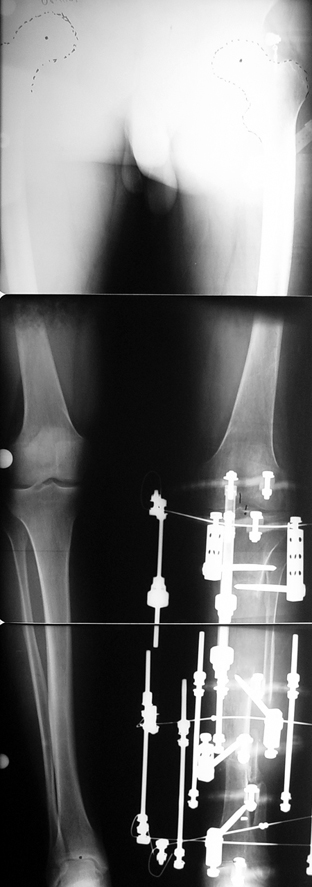

Uygun radikal debridman tüm nekrotik kemik ve yumuşak dokuların çıkartılmasını gerektirir, ve sıklıkla uzuvda instabiliteye neden olur. Kalan kemik ve yumuşak doku defektinin bir şekilde fiksasyonu ve rekonstrüksiyonu gereklidir. İlizarov’un ortaya koyduğu distraksiyon osteogenezi yöntemi, kaynamanın elde edilmesi, deformitenin düzeltilmesi, bacak boy eşitsizliğinin giderilmesi ve segmental defektlerin rekonstrükte edilmesi için başarıyla kullanılmaktadır.

Eksternal fiksatör ile geçen süre (eksternal fiksasyon indeksi), gereken distraksiyon miktarına bağlıdır ve bu süre boyunca bazı komplikasyonlarla karşılaşılabilir. Distraksiyon dönemi sona erdikten sonra, distraksiyon süresinin iki katını aşan konsolidasyon döneminde hastalar eksternal fiksatörü zorlukla tolere edebilirler. Yeterli konsolidasyon sağlanmadan eksternal fiksatör çıkartılırsa ise kırıklar, deformite ve kısalık oluşabilir. Hastanın fiksatör ile birlikte geçirdiği sürenin azaltılması ve böylece hasta konforunun ve aktivite düzeyinin arttırılması için intramedüller çivi üzerinden uzatma yöntemi uygulanmaktadır. Bu yöntemde distraksiyon dönemi sona erdiğinde kemiğin içindeki çivi statik olarak kilitlenmekte ve eksternal fiksatör çıkartılmaktadır. Stabilizasyon intramedüller çivi tarafından sağlandıktan sonra konsolidasyon dönemi gerçekleşmektedir. Bu şekilde hem eksternal fiksatörün uzun süre kalmasından hem de erken çıkartılmasından kaynaklanan komplikasyonların önüne geçilmektedir.

Vaka 2